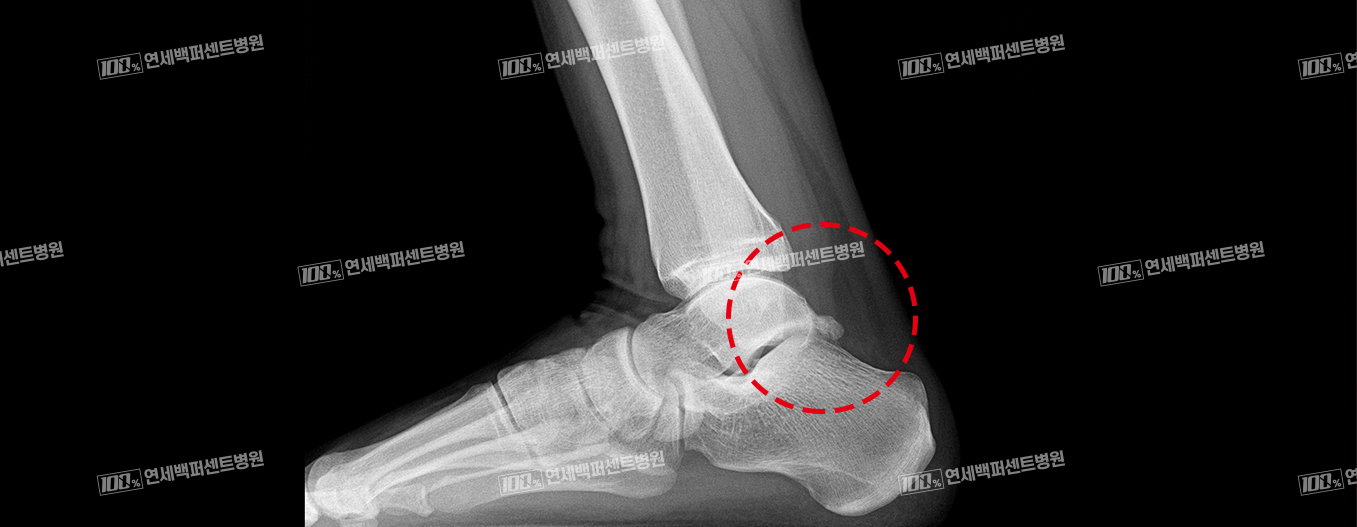

X-ray 소견

후방충돌증후군(삼각골증후군)은 발목뼈 뒤쪽에 분리되어 있는 뼈조각과

그 뒤를 지나가는 힘줄이 충돌하면서 염증이 발생하는 질환!